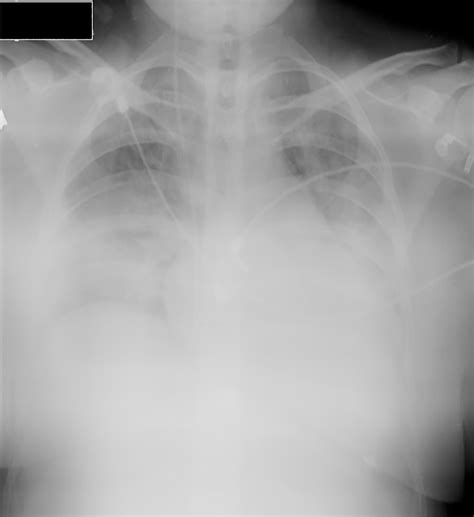

Oxygen Therapy Via Nasal Cannula Procedure - Adult Oxygen Cannula - Hibernia Medical : Furthermore, without an arterial cannula for repeated.. A dog with aspiration pneumonia receives oxygen supplementation via nasal prongs. What is the difference in oxygen use between a transtracheal catheter and nasal cannula? Able to deliver adequately heated and humidified medical gas at flows up to 60 l/min, it is considered to have a number of physiological advantages. Intubation procedure setup and technique. Survey of german ards centers and scientific evidence.

1000+ images about CME - Oxygen Therapy on Pinterest | Nursing, Pulse oximetry and Paramedics from s-media-cache-ak0.pinimg.com Nasal prong oxygen therapy also shows promise but requires further evaluation. Nasal oxygen therapy can be used for patients with acute severe hypoxemic. This article outlines when oxygen therapy should be used and the procedures to follow. Review key therapeutic techniques in this brief but comprehensive guide. Furthermore, without an arterial cannula for repeated. The nasal cannula (nc) is a device used to deliver supplemental oxygen or increased airflow to a patient or person in need of respiratory help. Intubation procedure setup and technique. Oxygen is distributed via copper pipes circulating from a central source, that is situated outside the building.

Nasal cannulas nasal cannulas are used for their simplicity and patient convenience. This article outlines when oxygen therapy should be used and the procedures to follow. Therapy of acute respiratory distress syndrome: This device consists of a lightweight tube which on one end splits into two prongs which are placed in the nostrils and from which a mixture of air and oxygen. Oxygen therapy via nasal cannula. Basics of nasal cannula application. Oxygen is distributed via copper pipes circulating from a central source, that is situated outside the building. And subsequently to endotracheal intubation. Nasal oxygen therapy can be used for patients with acute severe hypoxemic. Pilot study.journal of miyamoto, k. Nasal dryness discomfit in individuals receiving dry oxygen via nasal cannula respiratory care. Procedure for delivering oxygen therapy 40. Exhaled air dispersion during highflow nasal cannula therapy versus cpap via different masks.